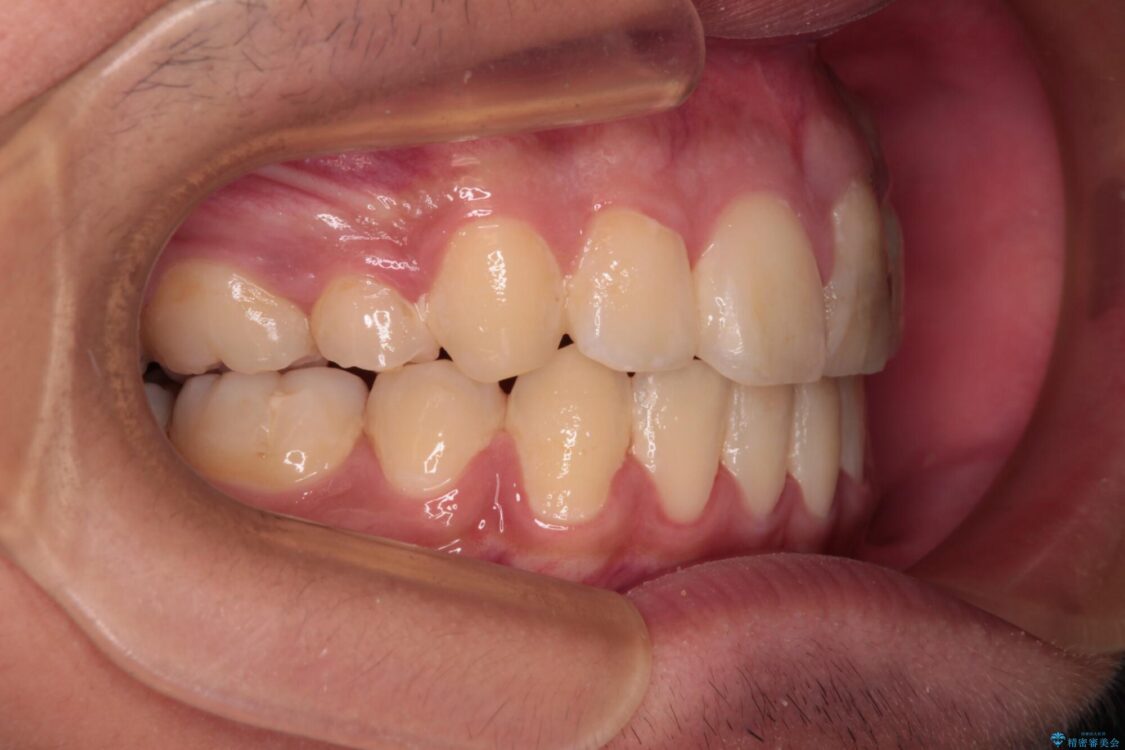

治療途中

• 膨らんだ口元 ワイヤー装置での抜歯矯正 治療途中画像